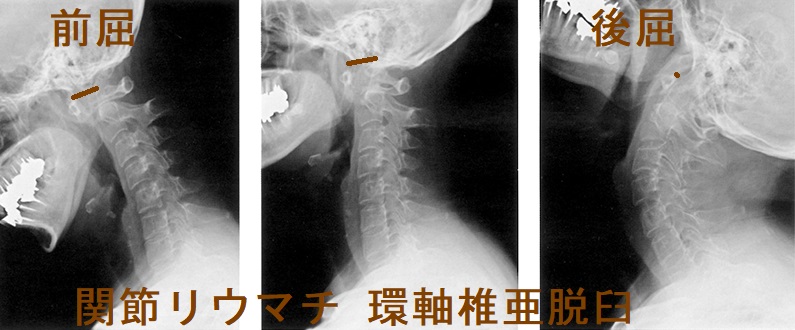

環軸椎亜脱臼

環軸椎亜脱臼は、第1頸椎(環椎)と第2頸椎(軸椎)を接合する環軸椎関節がずれて生じます。関節リウマチでは、環軸椎関節を接合する①環椎横靱帯の滑膜炎、②軸椎歯突起の破壊などにより環軸椎亜脱臼します。ダウン症候群でも環軸椎亜脱臼と甲状腺疾患の合併が多い[ダウン(Down)症候群と甲状腺の病気]。

環軸椎亜脱臼では、前屈位もしくは通常立位頸椎X線写真側面像の環椎歯突起間距離(atlantodental interval:ADI)が5 mm 以上になる(正常3 mm 以下)。後屈位でADIが正常範囲になる場合がある。